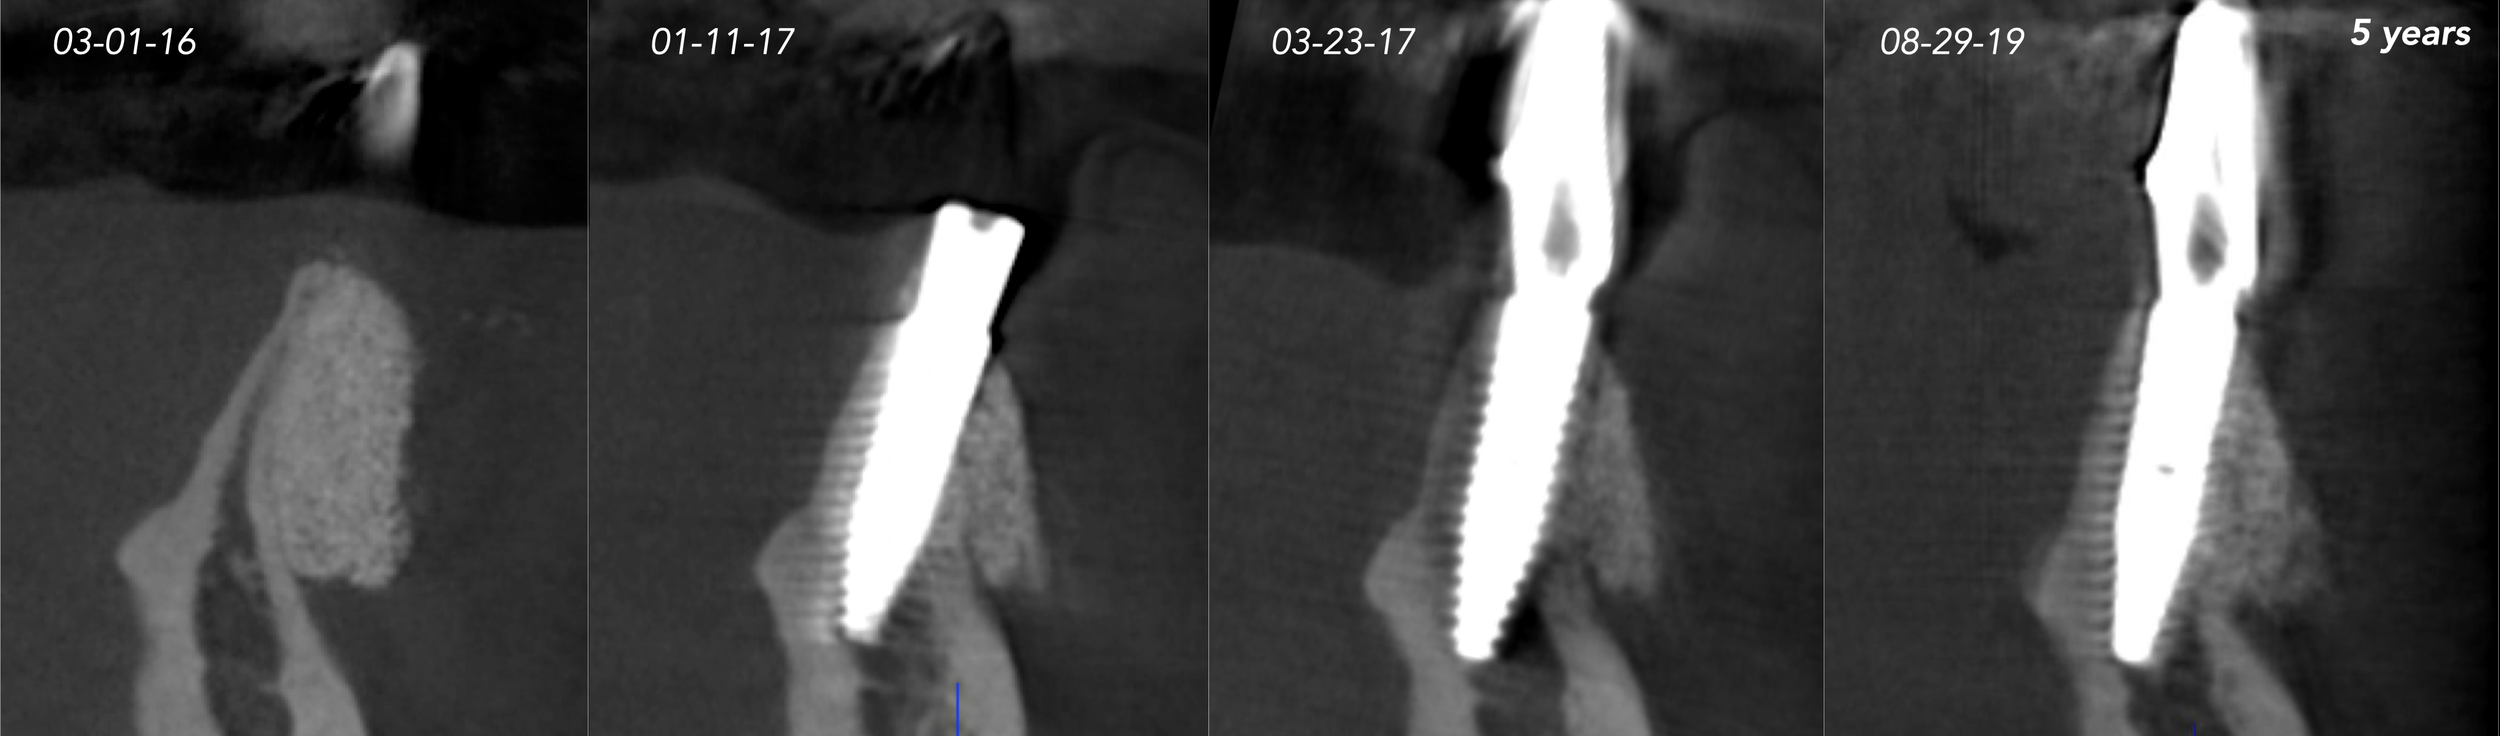

CASE 7. KNIFE-EDGE RIDGE

CASE 8. IMMEDIATE IMPLANT AND SIMULTANEOUS S.M.A.R.T.® HORIZONTAL AUGMENTATION